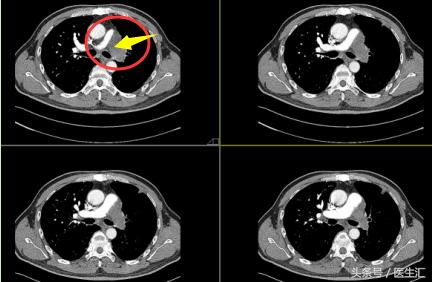

故患者 CTPA 如下图所示:

根据CTPA的图像显示,患者主动脉尚可,肺动脉只有右边的分支还行,另一边完全被栓塞了。那么和一般的肺栓塞也不完全一样,故医院先以“肺动脉栓塞?”收入院。